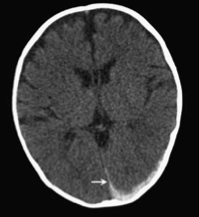

He stayed in the field until 1992, as improvements in medical imaging and surgical technique transformed the way doctors diagnose and treat problems of the brain. Neurosurgeons were collaborating with radiologists as they honed their abilities to decipher the lights and shadows of CT scans and MRIs. “I loved every minute of it,” he beams.

Her condition deteriorated, however, and diagnositic scans revealed brain swelling, which peaked about 24 hours into hospitalization. She was left with permanent brain damage, and doctors concluded that a short fall could not cause such a serious injury. Their reports included opinions that “retinal hemorrhages indicate that there was a rotational component to this, such as may be seen with shaking” and “[i]f the victim suffered these injuries on Saturday evening, she would not have survived until Sunday morning.”